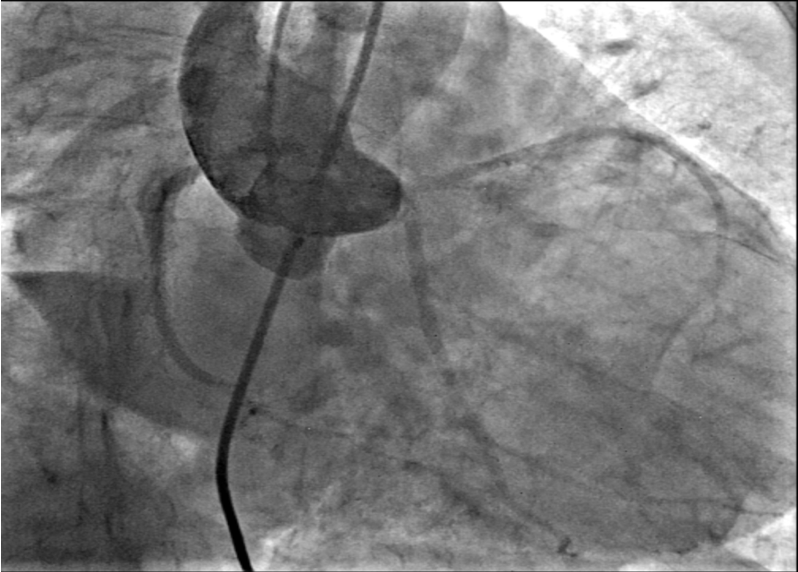

Ultrasound-guided dual access was completed, with a right femoral arterial as well as a venous approach. An aortogram was performed using the arterial approach, following introduction of a pigtail catheter at the level of the non-coronary aortic sinus, which showed a connection between the right atrium and the non-coronary aortic sinus (Figure 1, Video 1).

Figure 1. An aortogram revealing a communication between the right atrium and the non-coronary sinus of Valsalva (white arrow).

1. An aortogram was performed to confirm the presence and characteristics of the ruptured SVA and to assess the severity of associated aortic regurgitation.